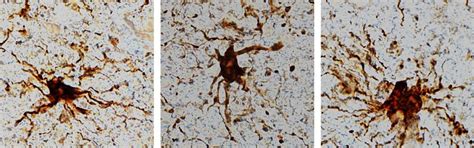

Neuroinflammation in Parkinson’s Disease: From Gene to Clinic: A ...

mdpi.com